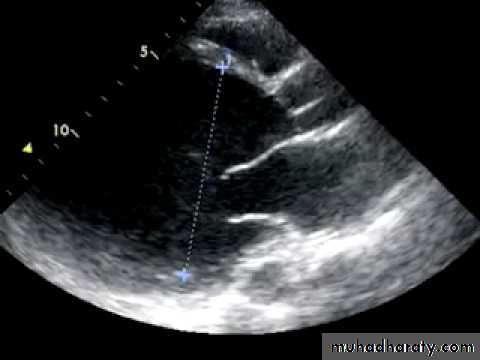

Echocardiography.

Two-dimensional and Doppler echocardiography establish the presence of systolic and/or diastolic impairment of the left or right ventricle.They may also reveal the aetiology (valve disease, regional wall motion abnormalities in ischaemic heart disease, cardiomyopathy, amyloid),

it may detect intracardiac thrombus.

An ejection fraction of < %55 is generally accepted as evidence for systolic dysfunction.

Doppler echo